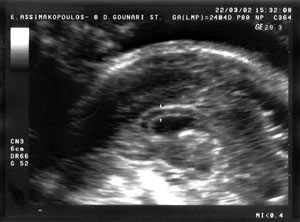

ΠΕΡΙΠΤΩΣΗ

2

Έγκυος 29 ετών, δευτεροτόκος, προσήλθε για υπερηχογράφημα δευτέρου επιπέδου

στις 21 εβδομάδες της κύησης. Αν και η βιομετρία του εμβρύου ήταν φυσιολογική,

παρατηρήθηκαν οι εξής ανατομικές ανωμαλίες: α) απουσία του μεσολοβίου, β) λυκόστομα-λαγόχειλο,

και γ) έλλειψη της παρεγκεφαλίδας με διάταση της μεγάλης δεξαμενής (cisterna

magna). Λόγω του ασύμβατου με τη ζωή ακολούθησε διακοπή της εγκυμοσύνης. Τα

προγεννητικά υπερηχογραφικά ευρήματα επιβεβαιώθηκαν με τη νεκροτομή του εμβρύου.

Στην εικόνα 6 διακρίνεται, όπως και στην εικόνα 3 (της περίπτωσης 1), το έμμεσο

υπερηχογραφικό εύρημα σχήματος σταγόνας δακρύου (tear drop shape) από τη διάταση

των πλαγίων κοιλιών, σε εγκάρσια διατομή. Στην εικόνα 7 διακρίνεται το λυκόστομα-λαγόχειλο,

ενώ στην εικόνα 8 απεικονίζεται ο οπίσθιος κρανιακός βόθρος με την έλλειψη της

παρεγκεφαλίδας και τη διάταση της μεγάλης δεξαμενής.

Εικόνα

6. Στην περίπτωση 2 διακρίνεται το έμμεσο υπερηχογραφικό εύρημα σχήματος

σταγόνας δακρύου (tear drop shape) από τη διάταση των πλαγίων κοιλιών, όπως

και στην περίπτωση 1, εικόνα 3.